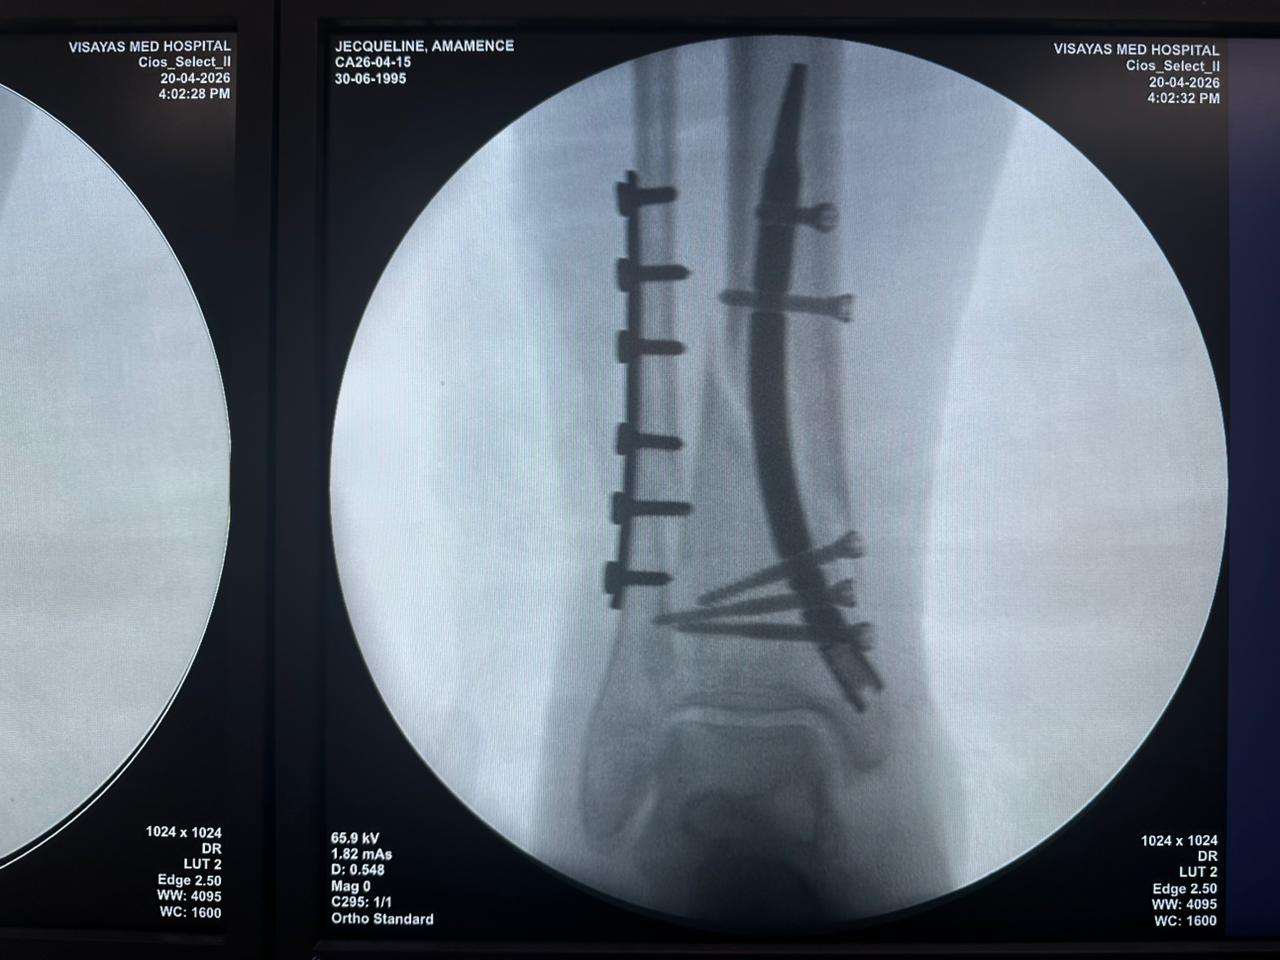

Distal Tibial Nail Fixation Case Study with Fibular Plate Support

Imaging:

Intraoperative C-arm fluoroscopy, AP and lateral views

Case Summary:

This case involved distal tibial fixation using an intramedullary distal tibial nail. Intraoperative fluoroscopy confirmed the position of the nail, distal locking screws, and fibular plate fixatio